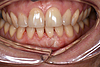

Cette dent présente une récession gingivale qui a favorisé l'apparition d'une carie.

La réalisation d'une greffe gingivale a permis de protéger la racine et de préserver l'avenir de la dent.